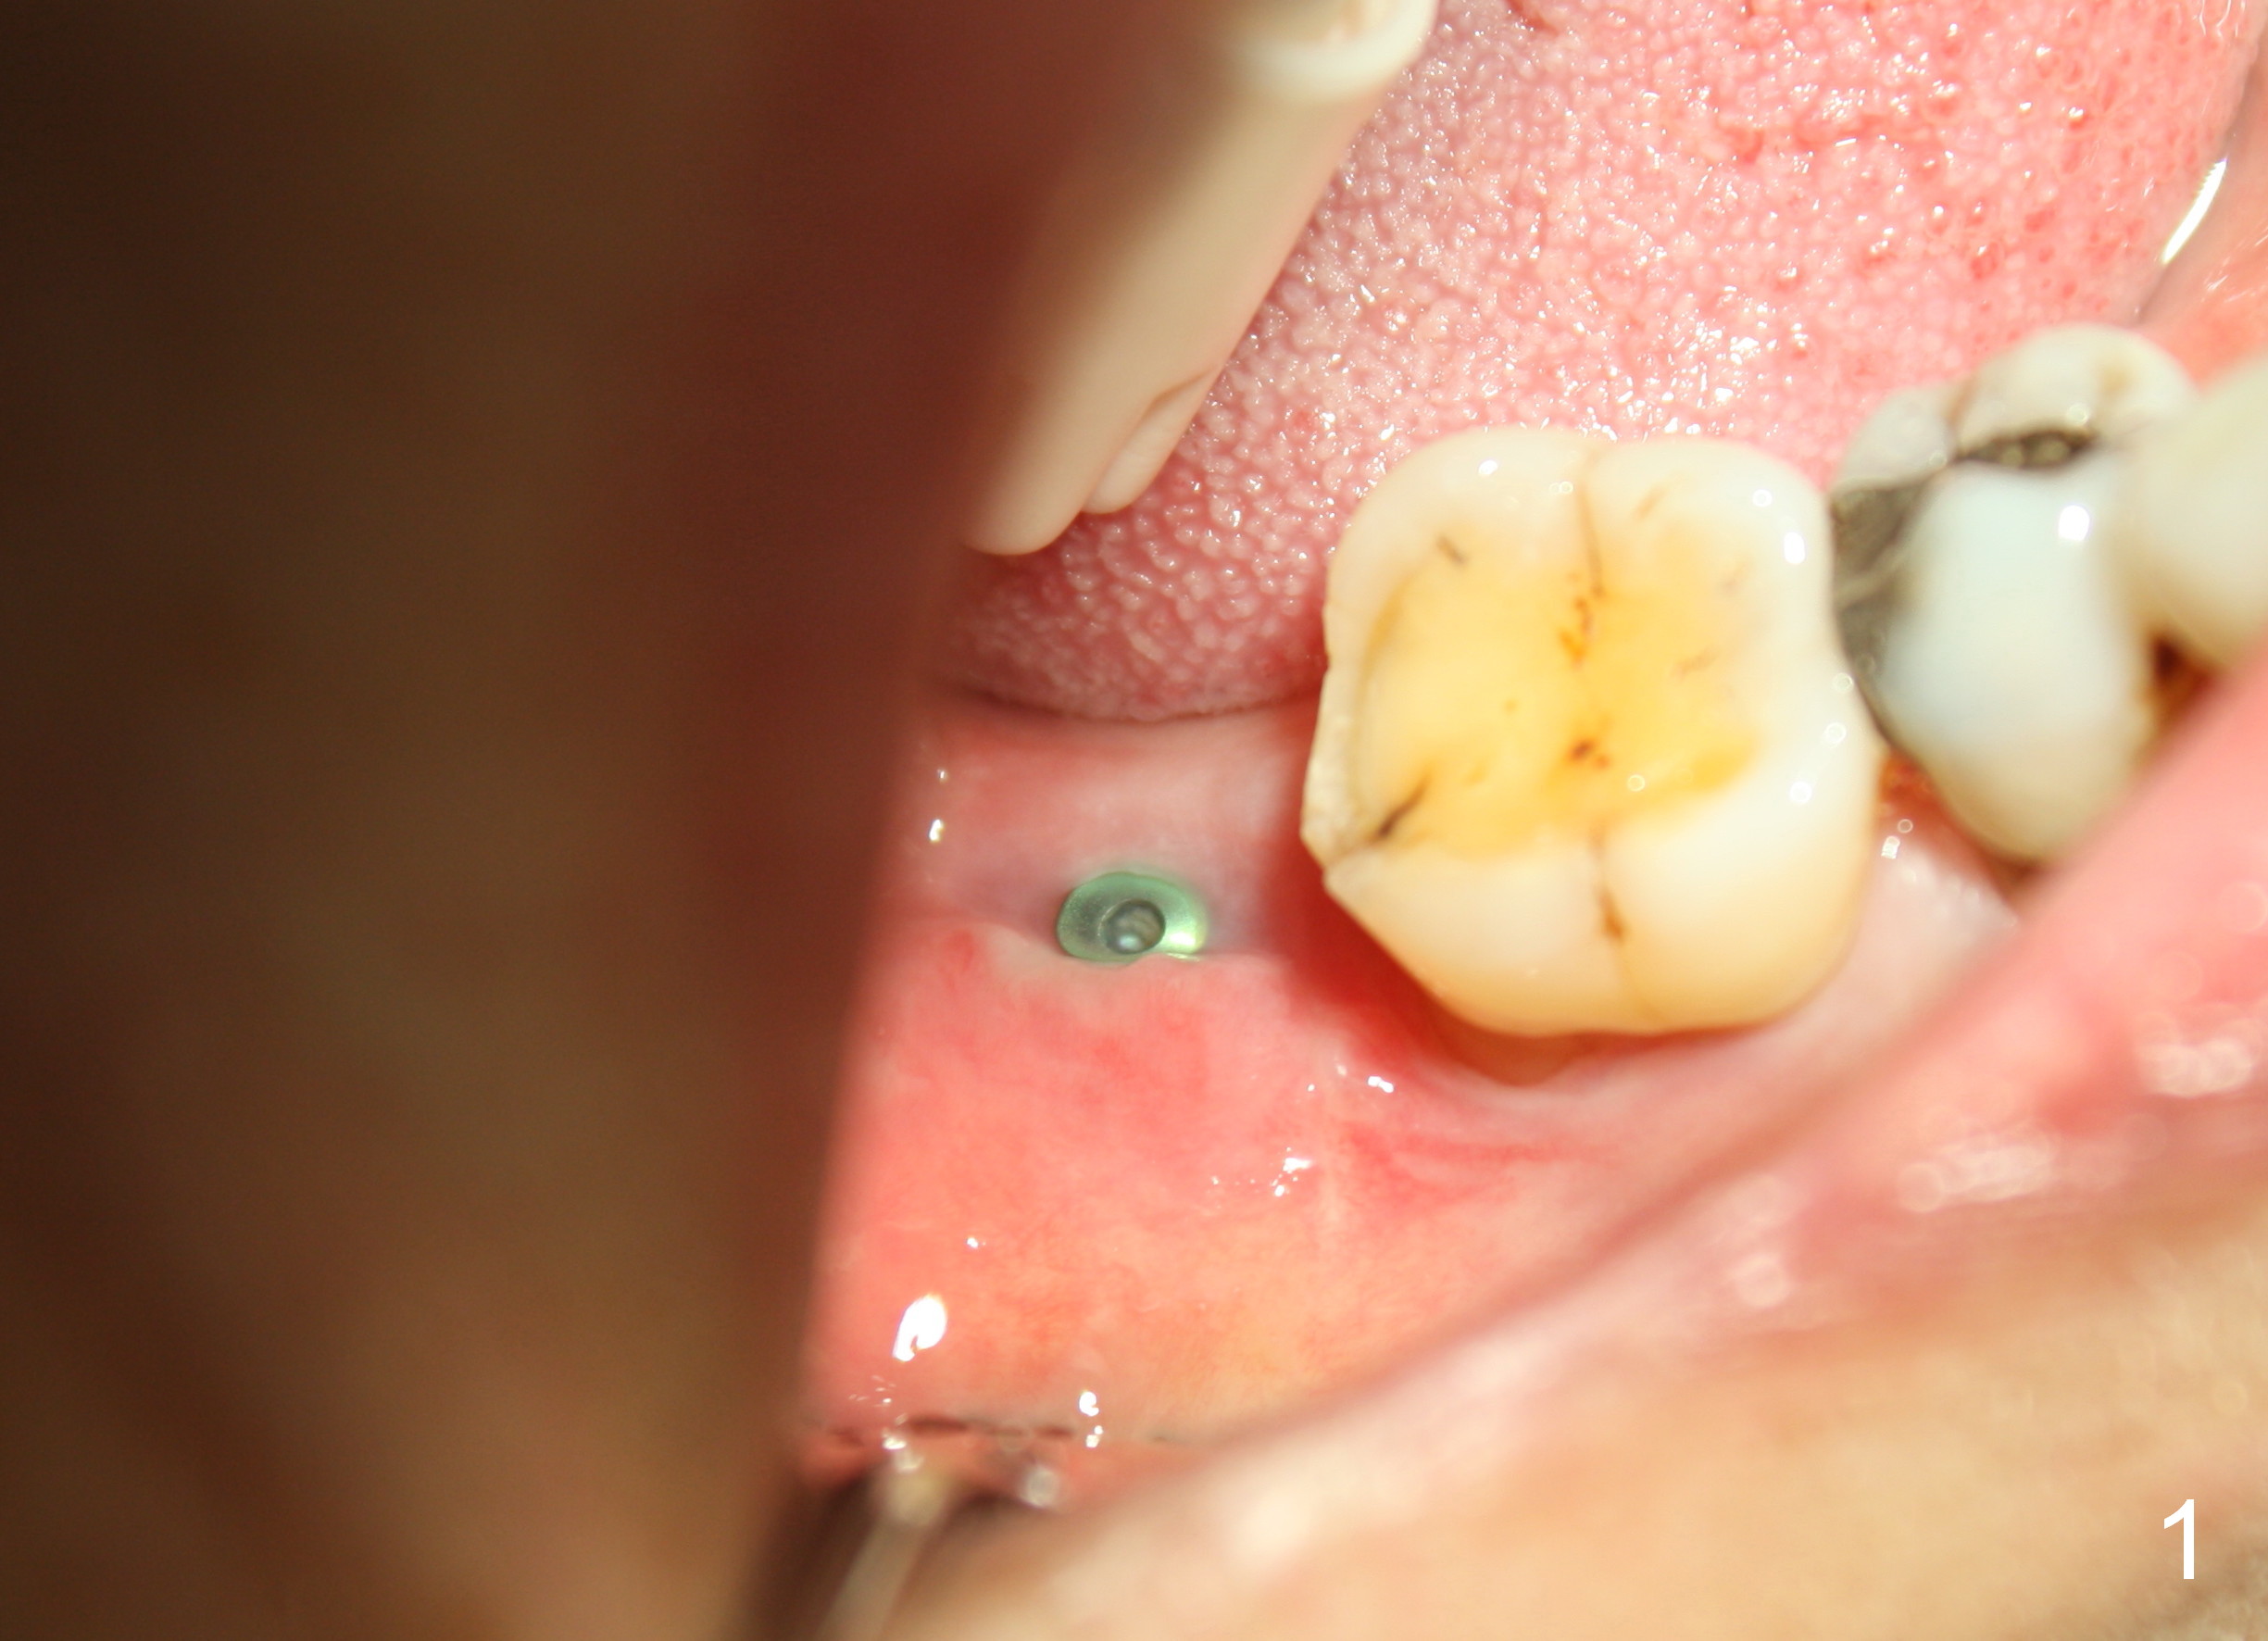

The wound of 2 stage implant surgery is found to be gapping 10 days postop with healing screw exposure 2 weeks postop. Exam at a month postop (Fig.1) shows that the mesiolingual cusp of the upper right 2nd molar is sharp (Fig.2 <) and inserted into the wound of the implant site (Fig.3). Two mini-implants are placed with immediate power chain retraction (Fig.4). The orthodontic intrusion is without effect; brackets are placed 4 months later (Fig.5). Two months later, the patient is diagnosed to have breast cancer. As a precaution for chemotherapy, the orthodontic device is removed. During chemotherapy, the patient returns once. The gingiva around the cover screw is mildly erythematous and edematous. After removing plaque from the cover screw with irrigation, the patient feels a little better. All of the orthodontic appliances are removed before she receives chemotherapy for breast cancer.